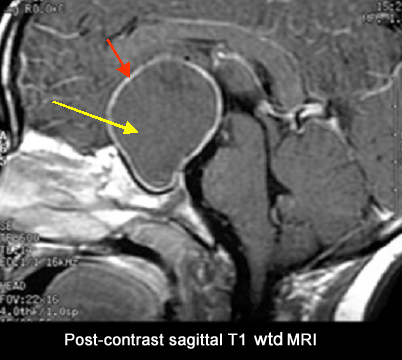

Craniopharyngioma

Findings : A large cystic suprasellar tumor (yellow arrow) with a rim of peripheral enhancement (red arrow).

• Common suprasellar tumor in a child.

• Tumors can be cystic/solid.

• Common calcified tumor; calcification within the tumor can be seen as high as 90%.